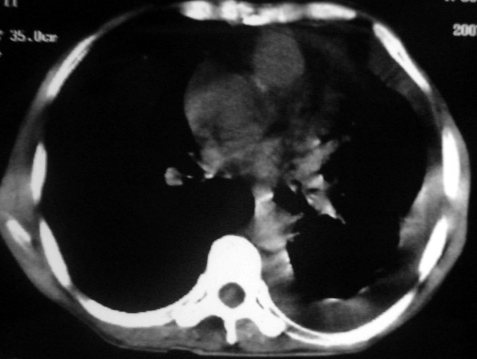

男,54岁,咳嗽,气喘半年,胸痛一月.

血性胸水

左肺下叶中心型肺癌,伴阻塞性肺炎、左胸腔积液、心包少量积液。

考虑左下叶中心型肺癌,伴阻塞性肺炎,左胸腔积液,心包积液,建议纤支镜检查